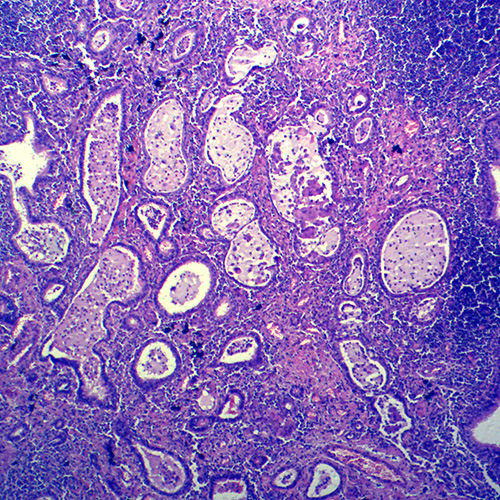

四川炎症病理玻片